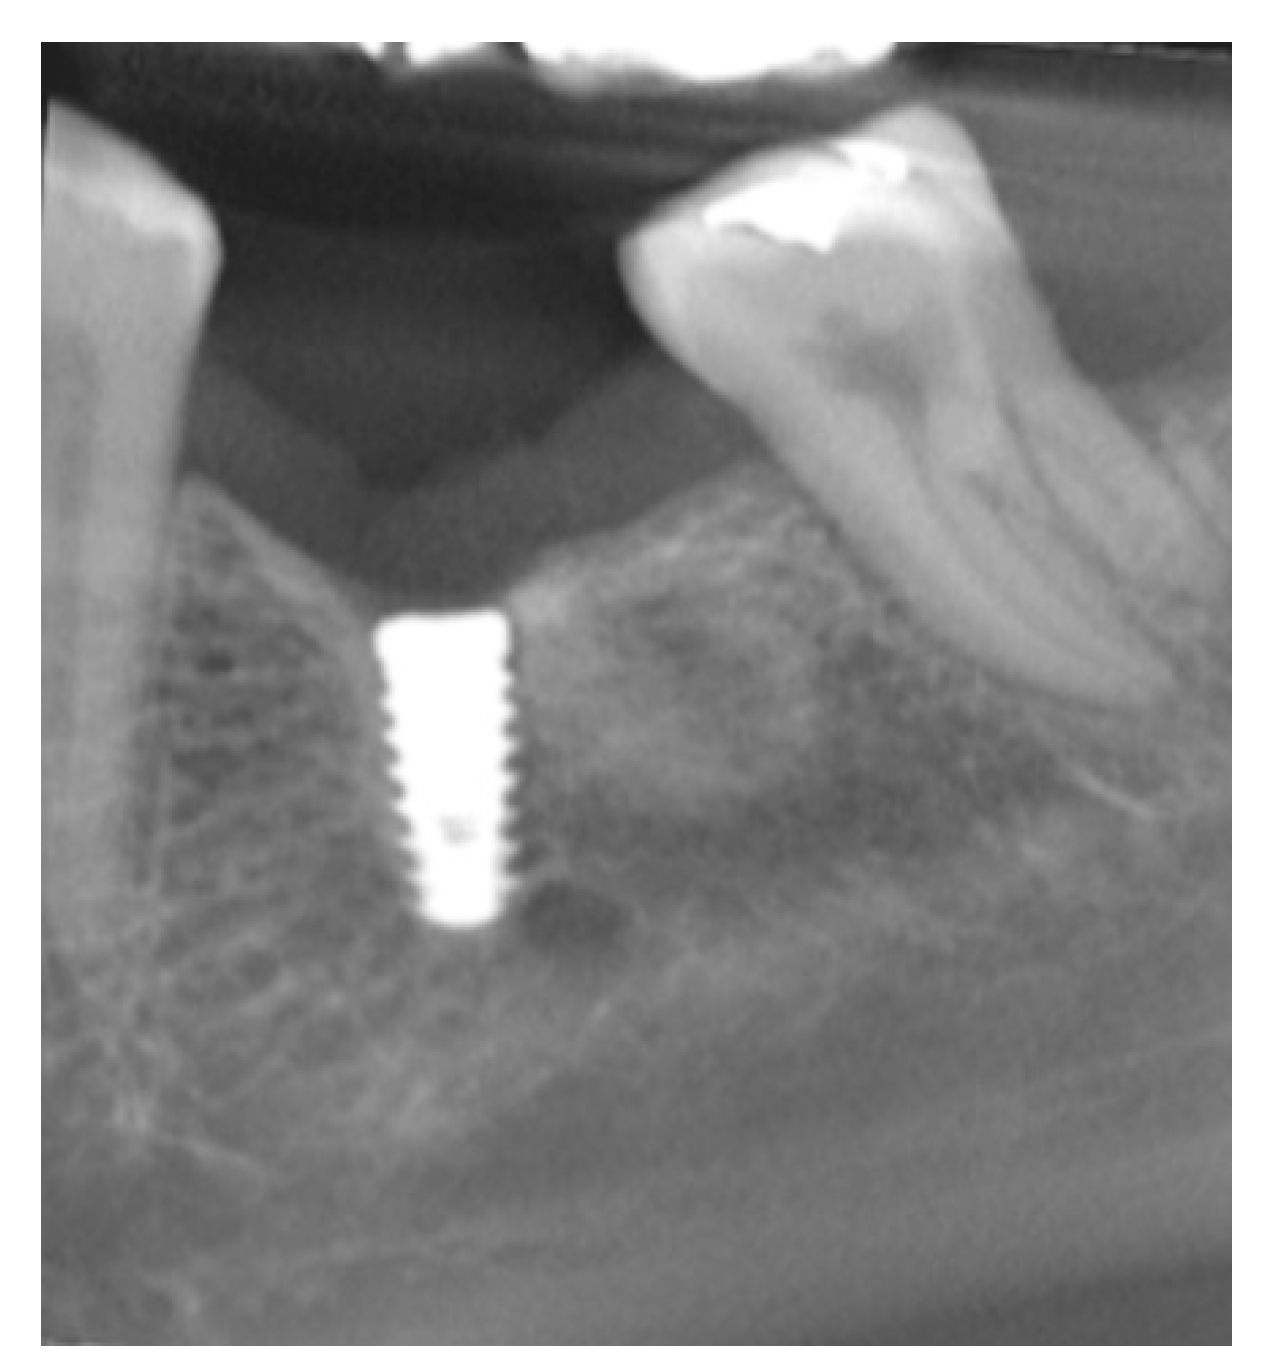

2.3. Radiographic Evaluation